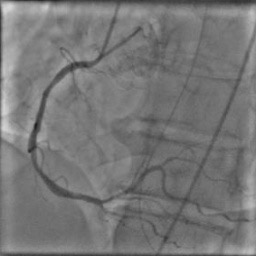

X-ray angiography is the most used imaging modality to visualise blood vessels for interventional purposes such as stenting of stenosed vessels or for diagnostic purposes such as assessment of myocardial perfusion or stenosis grading. To minimise ionising radiation exposure of the patient and medical personnel during image acquisition, low power X-Rays are used resulting in noisy and low contrast images. In the context of diagnosis, the main object of interest is the vascular tree, its branchings and variations in thickness. It is therefore necessary to accurately highlight the vessels in consecutive frames to reduce the noise and improve contrast. In addition, in interventional procedures, identifying interventional instruments (catheter, wires) is also needed in order to better plan and control their positioning. Efficiently discriminating between instruments and vessels as well as other anatomical structures that may have similar appearance is crucial during the interventions. Figure 1(a-c) shows an example of an angiogram sequence. Note large non-rigid motion between frames as well as the ambiguity between vessels and the catheter. Figure 1(e) shows a frame from a different sequence of the same patient but taken at different scan and angle and (f) shows a different patient. There is a significant difference in vessel as well as catheter locations in all three sequences, which we consider as independent examples. Figure 1(d) shows the ground truth segmentation of the first frame.

Dataset

The dataset consists of anonymised fluoroscopy X-Rays of 26 different patients. The images were acquired during stent placement using a General Electric Innova 2000 system and stored according to standard medical protocol in DICOM format. In total the dataset includes 36000 frames corresponding to 365 distinct video sequences with an average of 98 frames each. Different sequences of the same patient were taken at different angles and stages of the procedure therefore they differ significantly as shown in Figure 1(c)(e)(f). Each frame is rescaled from to due to memory constraints.